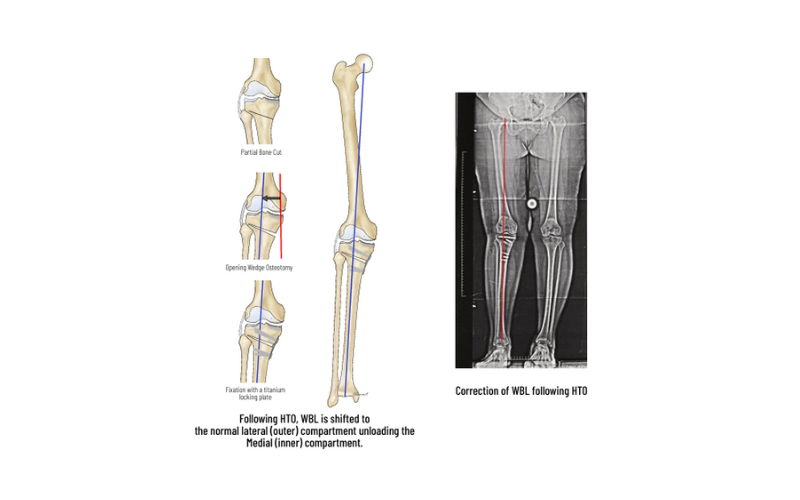

HTO-High Tibial Osteotomy

HTO is a procedure to correct the alignment and redistribute the load to the non-involved compartment. Arthroscopy is performed to assess the status of the joint and to treat meniscal tears, loose bodies, and cartilage tears. Based on preoperative planning and using precision instrumentation, a partial bone cut (osteotomy) is made in the upper tibia and is slowly opened to the desired level to shift the load to the normal compartment. The osteotomy is fixed with strong PEEK or titanium plates to allow early movements and weight-bearing. HTO also protects procedures like meniscus repair and cartilage repair by unloading the joint. HTO can postpone the need for knee replacement for many years.